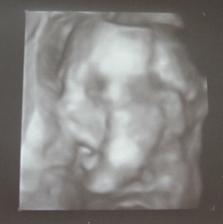

10.12.2007 - byli jsme na 3D ultrazvuku, máme asi 17 minutový záznam miminka a na 99% určené pohlaví (ale zatím je to TAJEM)